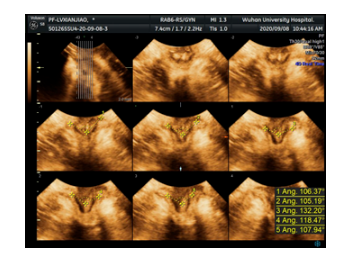

盆底四维超声报告:

前腔室:膀胱颈移动度增大、膀胱后角开放、膀胱轻度膨出声像;

中腔室:子宫脱垂声像;

后腔室:可见肠疝声像、直肠脱垂声像;未见肛提肌断裂声像;肛门内外括约肌完全断裂声像;肛提肌裂孔扩张。